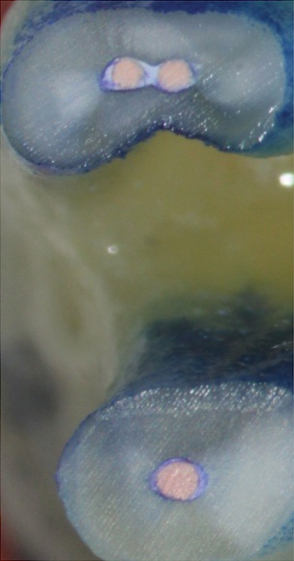

Figure 16. Post apicoectomy. Courtesy of Dr. Sam Kratchman.

Figure 16

Figure 17. Retropreps and isthus filled. Courtesy of Dr. Sam Kratchman.

Figure 17